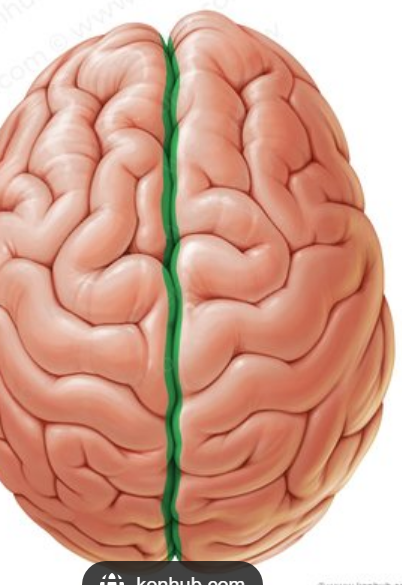

fissura longitudinalis cerebri